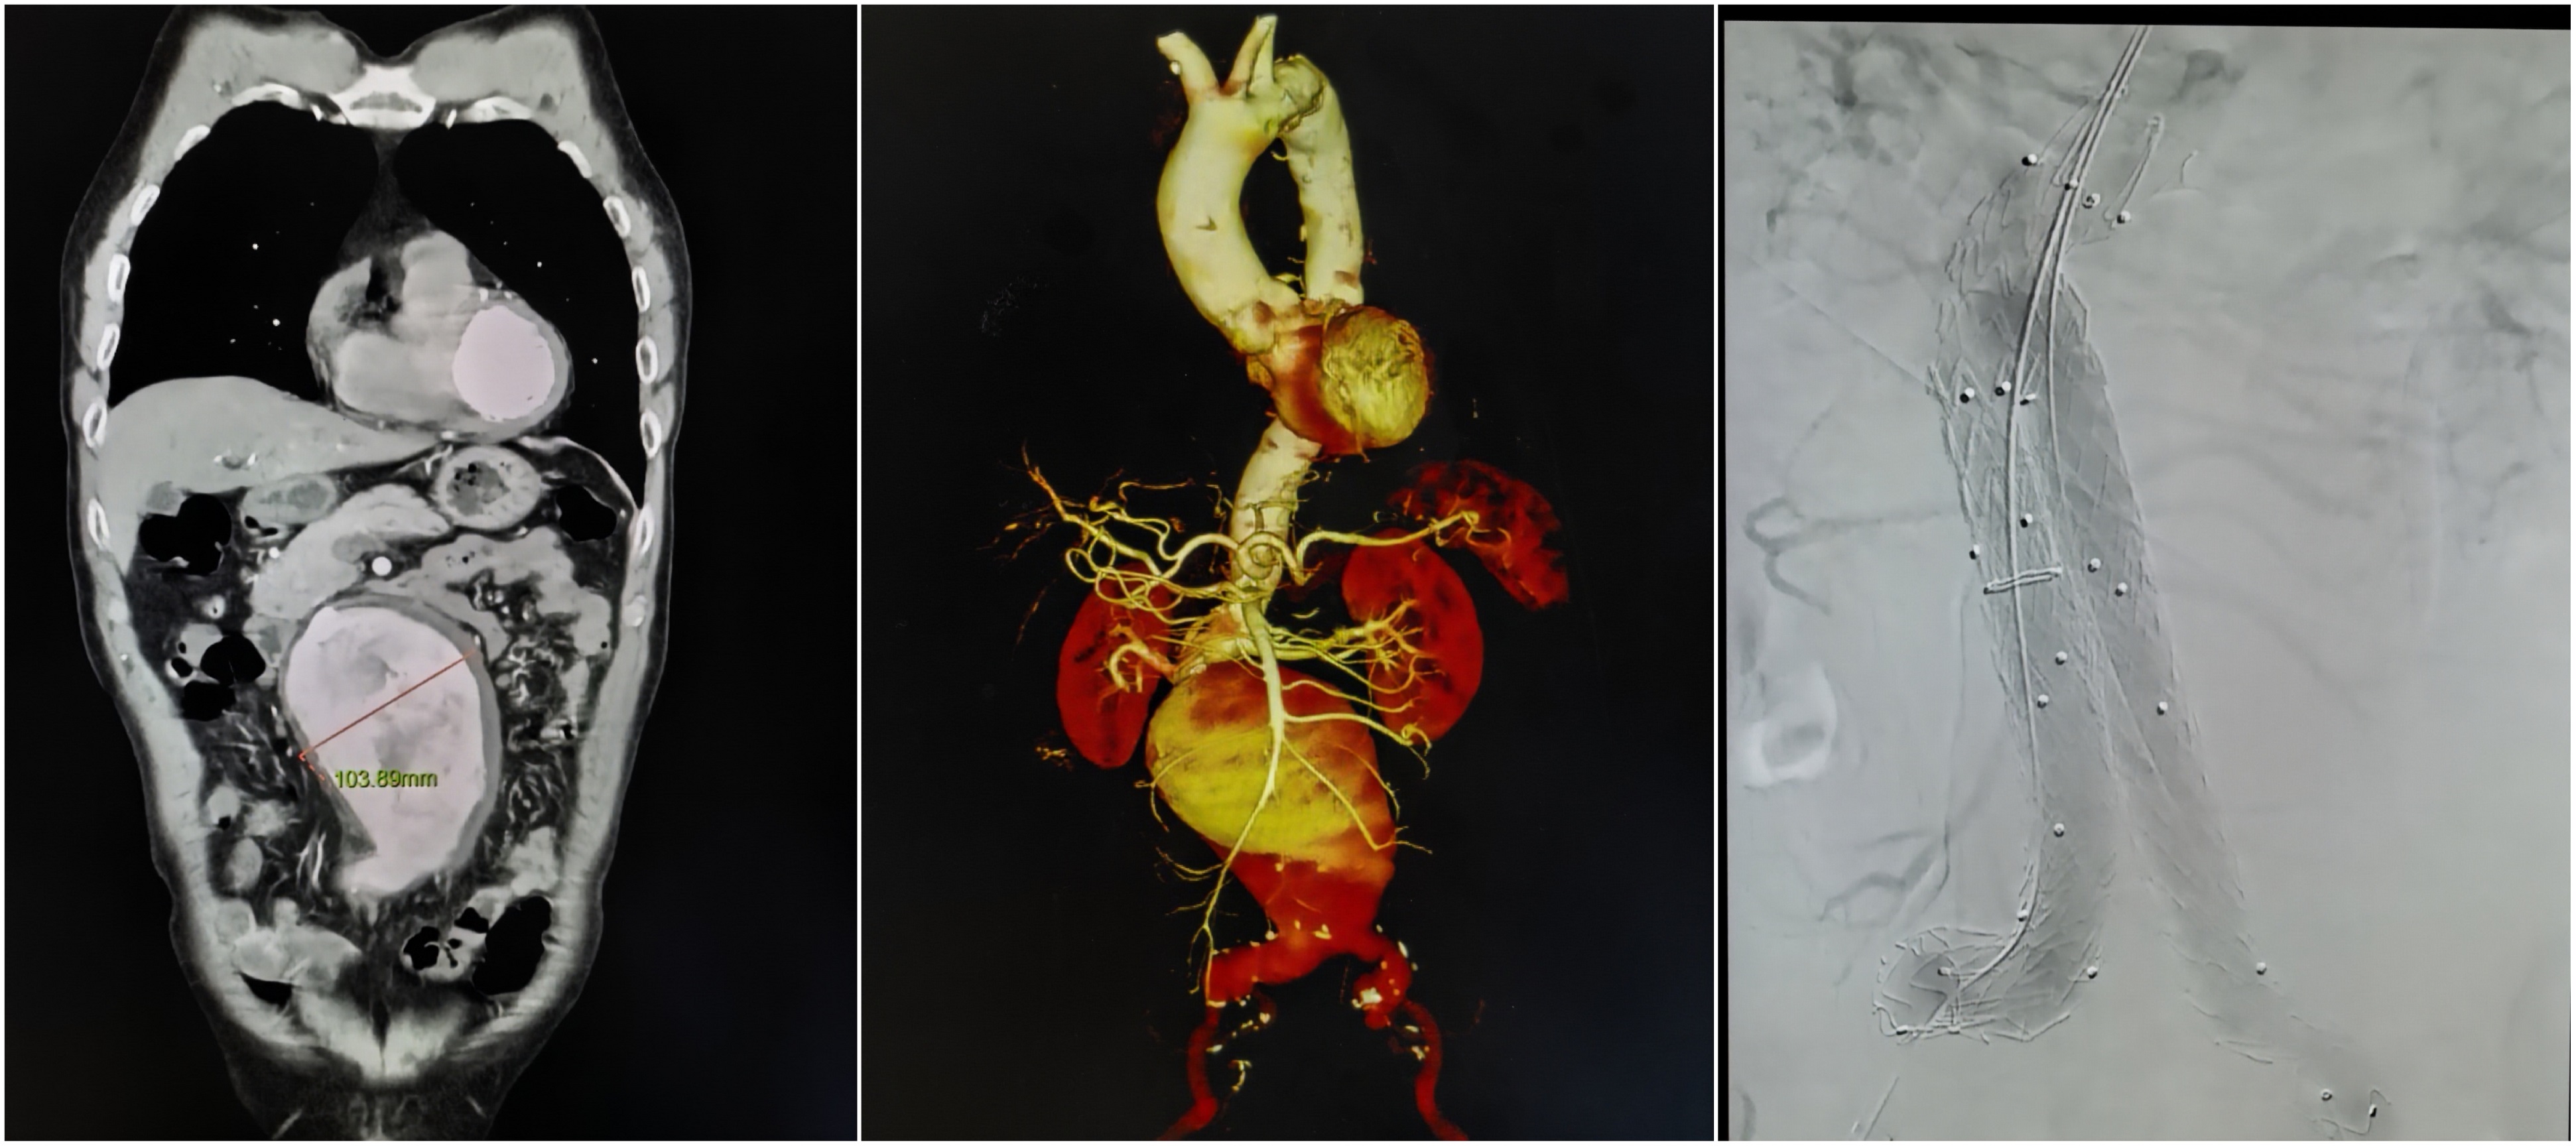

血管外科微创“拆弹”成功救治10cm巨大腹主动脉瘤先兆破裂患者

4月23日,中南大学湘雅三医院上演一场惊心动魄的生命急救。血管外科团队高效联动、精准施治,成功为一名患有直径达10厘米的巨大腹主动脉瘤患者完成急诊微创腔内隔绝术,以精湛技术拆除体内“定时炸弹”。

患者因腹胀就诊湘雅三医院,CT意外发现腹主动脉巨大动脉瘤,濒临破裂,病情危急,血管外科总住院薛碧晨第一时间赶赴急诊科接诊,血管外科副主任徐宏博迅速启动危重动脉瘤急救绿色通道,在急诊科、麻醉科、复合手术室大力配合下,争分夺秒完成术前准备。随后,血管外科主任姚凯带领徐宏博、王智超、薛碧晨组成的“拆弹部队”仅用一个多小时,通过三个小于1cm的小切口完成微创介入手术,成功隔绝动脉瘤,复查无任何内漏,手术圆满成功。术后患者生命体征平稳,恢复情况良好,于今日从ICU顺利转回普通病房,恢复下地行走。

手术前后的动脉瘤对比